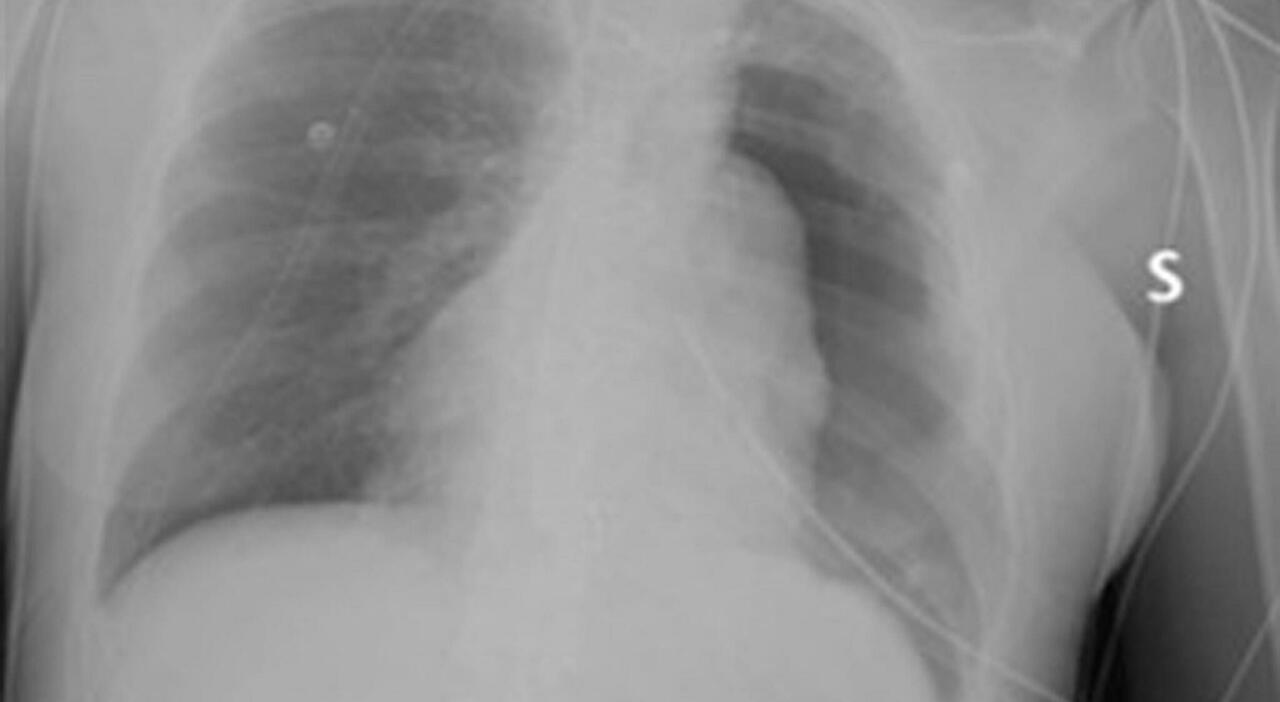

Dopo aver contratto il Covid-19, Sara ha notato un peggioramento delle sue condizioni respiratorie e si è sottoposta a una radiografia del torace, che ha rivelato la presenza di una massa voluminosa. Successive indagini hanno confermato il timoma, un tumore del timo che solitamente insorge in età adulta.

Sara (nome di fantasia) in seguito a un’infezione da Covid-19, notando un peggioramento delle sue condizioni respiratorie, affanno soprattutto da sforzo, dolore nella parte sinistra del torace, tosse secca stizzosa da tempo, si sottopone a una radiografia del torace. «La giovane donna presentava una massa molto voluminosa, che occupava tutta la parte centrale e la metà sinistra del torace», ricorda Maria Letizia Vita, dirigente medico presso la Uoc di Chirurgia toracica del Policlinico Gemelli.